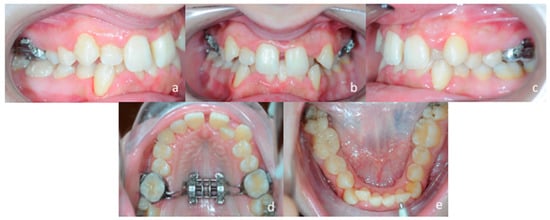

A 25 years old female attended consultation for orthodontic treatment to enhance the aesthetic of the smile. In particular, the chief complain was the crowded teeth along with the presence of wide buccal corridors while smiling. Facial analysis revealed retrognatic profile with labial competence, no gingival exposure during smiling along with extensive buccal corridors (Figure 7a–c). Intra-oral examination revealed class I molar and canine relationships, significant maxillary and mandibular crowding, mild maxillary transversal deficiency with cross-bite on the right side due to mandibular shift toward cross-bite side, significant anterior overbite (Figure 8a–e). Panoramic examination showed healthy condition of the upper first molars that would support the dental anchorage of the MSE device (Figure 9). Cephalometric analysis (Figure 10a,b) confirmed that the patient presented skeletal class I maxillo-mandibular relationship with retruded profile, mesiofacial growth pattern and anterior overbite. Patient approved the usage of photographic and radiographic records for the purpose of publication, by signing a specific form.

Figure 8.

Intra-oral patient’s examination. (a) Right lateral occlusion, (b) front view, (c) left lateral occlusion, (d) occlusal view of the maxillary arch, (e) occlusal view of the mandibular arch.